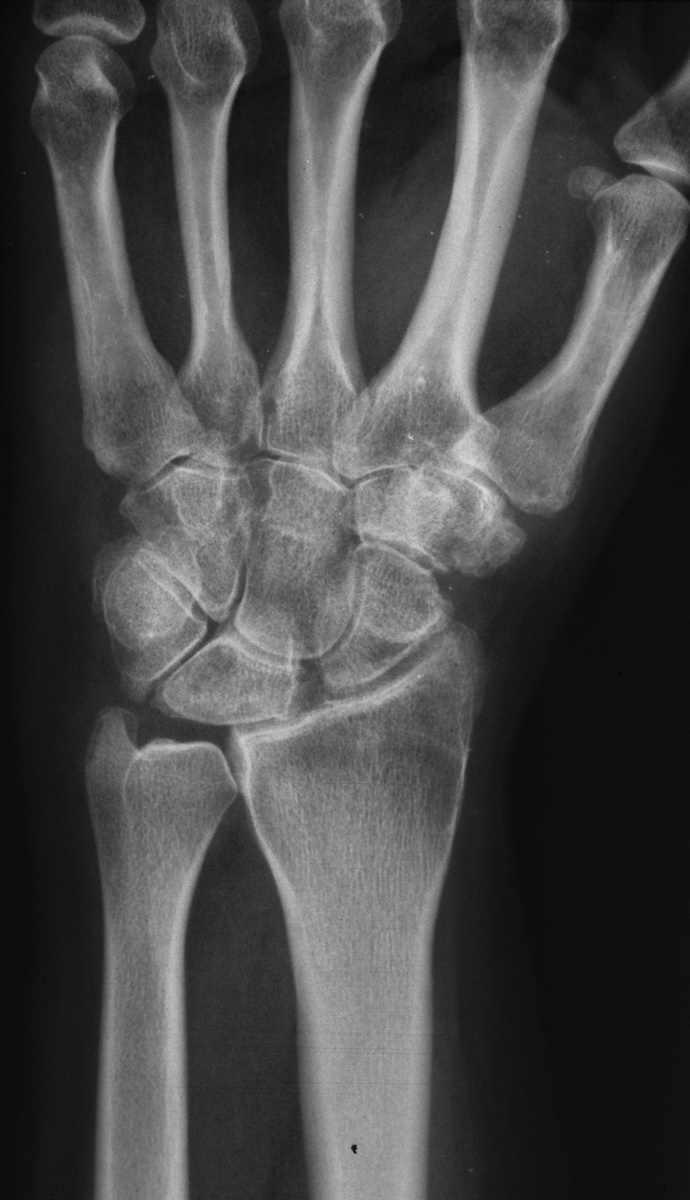

| Opposite side, asymptomatic: |